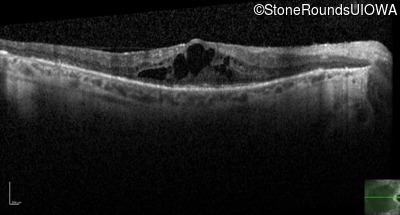

Age at visit: 46 years

This 46 year old man has had poor vision in dim light since age 2.

Diagnosis & molecular findings

AR Retinitis Pigmentosa SLC24A1 Met252 del2ggaAT Leu1052 del2ctTC AR